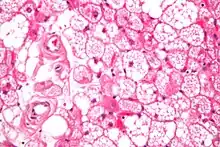

Micrograph of a hibernoma. H&E stain.

A high power hematoxylin and eosin stained photograph of a hibernoma.

The tumors histologically resemble brown fat. There are four histologic types recognized, but one is the most frequently seen (typical). There is a background of rich vascularity.

1. Lobular type: Variable degrees of differentiation of uniform, round to oval cells with granular eosinophilic cells with prominent borders, alternating with coarsely multivacuolated fat cells (pale cells). There are usually small centrally placed nuclei without pleomorphism. The cells have large cytoplasmic lipid droplets interspersed throughout.[3][4]

2. Myxoid variant: Loose, basophilic matrix, with thick fibrous septa, and foamy histiocytes

3. Lipoma-like variant: Univacuolated lipocytes, with only isolated hibernoma cells

4. Spindle cell variant: Spindle cell lipoma combined with hibernoma